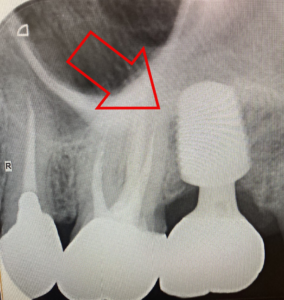

こちらがインプラント治療を終えた歯です。

その後、左上の一番奥の歯も同様の流れでインプラント治療を行いました。

治療後の全体の写真とレントゲン写真がこちらです。